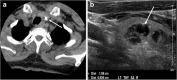

Focal and diffuse thyroid abnormalities are commonly encountered during the interpretation of computed tomography (CT) exams performed for various clinical purposes. These findings can often lead to a diagnostic dilemma, as the CT reflects the nonspecific appearances. Ultrasound (US) examination has a superior spatial resolution and is considered the modality of choice for thyroid evaluation. Nevertheless, CT detects incidental thyroid nodules (ITNs) and plays an important role in the evaluation of thyroid cancer. In this pictorial review, we cover a wide spectrum of common and uncommon, incidental and non-incidental thyroid findings from CT scans. We also discuss the most common incidental thyroid findings, best practices for their evaluation, and recommendations for their management. In addition, we explore the role of imaging in the assessment of thyroid carcinoma (before and after treatment) and preoperative thyroid goiter, as well as localization of ectopic and congenital thyroid tissue.